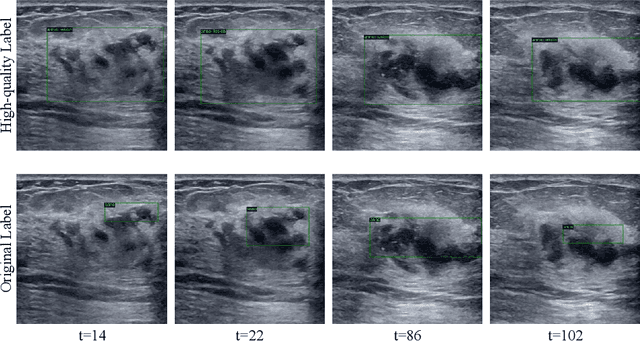

Abstract:During ultrasonic scanning processes, real-time lesion detection can assist radiologists in accurate cancer diagnosis. However, this essential task remains challenging and underexplored. General-purpose real-time object detection models can mistakenly report obvious false positives (FPs) when applied to ultrasound videos, potentially misleading junior radiologists. One key issue is their failure to utilize negative symptoms in previous frames, denoted as negative temporal contexts (NTC). To address this issue, we propose to extract contexts from previous frames, including NTC, with the guidance of inverse optical flow. By aggregating extracted contexts, we endow the model with the ability to suppress FPs by leveraging NTC. We call the resulting model UltraDet. The proposed UltraDet demonstrates significant improvement over previous state-of-the-arts and achieves real-time inference speed. To facilitate future research, we will release the code, checkpoints, and high-quality labels of the CVA-BUS dataset used in our experiments.